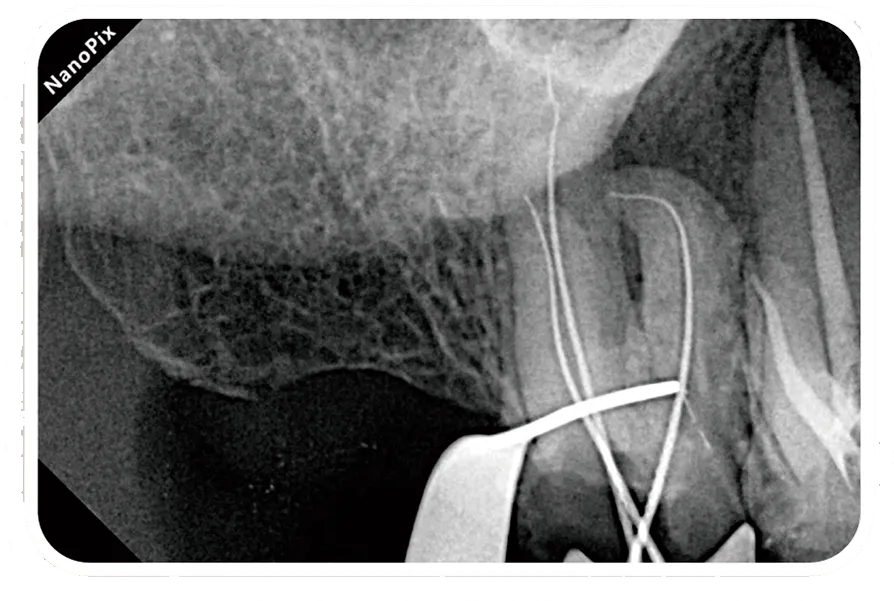

Клинические изображения

Чёткое изображение с высоким разрешением и фокальным пятном 0.4 мм